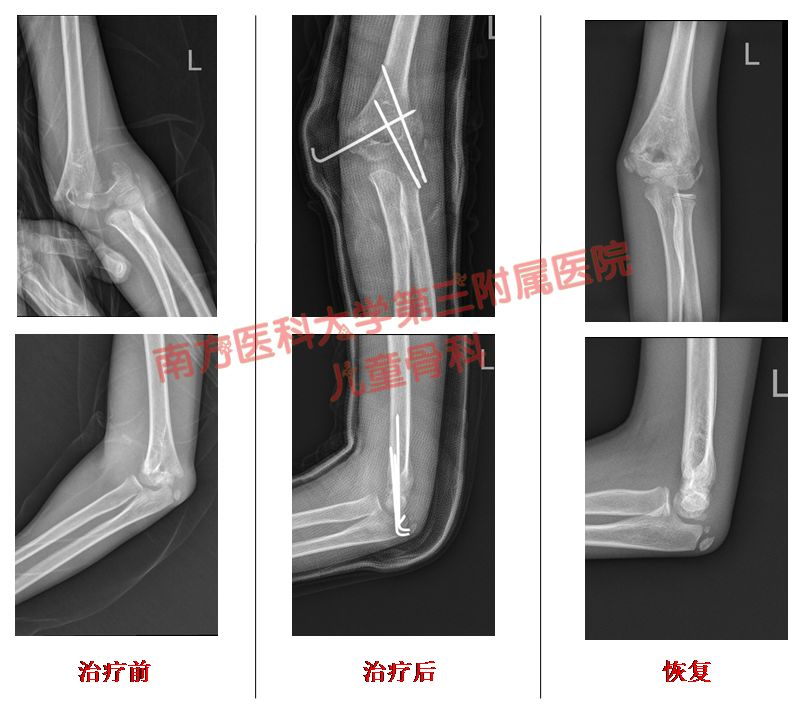

我科近乎“0”切开几率方式处理肱骨髁上骨折,麻醉下采用手法复位,克氏针交叉固定+石膏固定术,显著的减少了常规保守治疗肱骨髁上骨折高达30%的畸形率。

Ⅱ型*特中**殊的中尺侧有压缩的要手术治疗,复位不好容易往往导致畸形愈合,形成肘内翻。要先手法整复、经皮克氏针固定一个月,纠正畸形,维持坚强的内固定。

Ⅲ型这种程度就比较复杂和严重得多,也是需要要手术治疗,闭合复位,经皮克氏针固定。

病例2